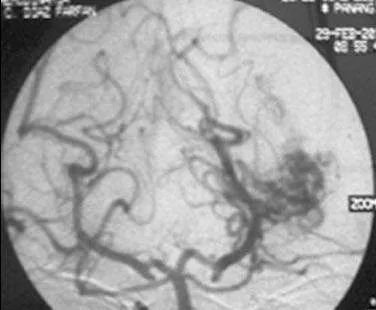

仅仅一次手术三个月后,令大卫一家一直恐惧的事情还是来临了。大卫在学校突然昏迷,紧急送往医院后,检查为左侧颞角的AVM导致脑室内出血。Spetzler-Martin分级4级:S1V1E1/A1B0C0),供血来自AChA(脉络膜前动脉)。

(a)左侧ICA造影,侧位]和lPChA

(b)左侧VA造影,前后位像